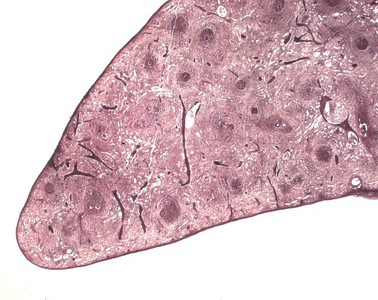

Präparat 35: Milz, Masson-Goldner

Milzknötchen

Folliculus lymphaticus splenicus, Malpighi-Körperchen (Achtung: auch die Nierenkörperchen werden nach ihrem Erstbeschreiber Marcellus Malpighi (1628 -1694) Malpighi-Körperchen genannt); als Primärfollikel ohne spezielle Innenstruktur oder als Sekundärfollikel vorkommende Milzfollikel. Als Sekundärfollikel verfügen sie über ein helles Reaktionszentrum mit großen Lymphozyten und eine dunklere Mantelzone aus kleinen inaktiven Zellen. Im Reaktionszentrum finden sich hauptsächlich B-Lymphozyten, B-Immunoblasten sowie T-Helferzellen. Die Follikel sind von einer eher unauffälligen Marginalzone umgeben, die sie von der roten Milzpulpa trennt. Gemeinsam mit den periarteriellen Lymphozytenscheiden bilden die Malpighi-Körperchen die weiße Pulpa der Milz.

Diese Vergrößerung zeigt die die einzelnen Abschnitte eines Milzknötchens. In der Mitte liegt das Keimzentrum (Reaktionszentrum) mit relativ großen Zellen, an das Keinzemtrum schließt sich die Korona aus dicht gepackten Lymphozyten mit kleinen kräftig gefärbten Zellkernen an. Umgeben wird die Korona von einer Marginalzone, der die perifollikuläre Zone folgt. In der perifollikulären Zone befinden sich Blutzellen bereits extravasal (offener Kreislauf).